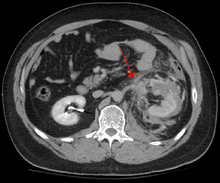

The imaging modality of choice is contrast-enhanced, computed tomography (CT) which is readily available in most emergency departments of moderate or above size. Scan times have become shorter with each generation of scanners and current scans are quick and accurately demonstrate renal injuries together with associated injuries to other abdominal or retroperitoneal organs.

Unlike ultrasound examination (FAST), CT provides anatomic and functional information that allows for accurate grading of the injury which is partly responsible for a growing trend toward conservative management (intravenous fluids, close monitoring, watchful waiting) of renal trauma.[5] Conservative management does not apply in situations where extensive urinary extravasation or devitalized areas of renal parenchyma are found and especially if associated with injuries to other abdominal organs; these cases are complication-prone and much more likely to require surgery. That being said, a retrospective study suggests that primary conservative treatment of blunt kidney rupture seems to lead to less surgery, especially less open surgery, and less blood and renal parenchyma loss, compared to a strategy of initial surgery.[6]